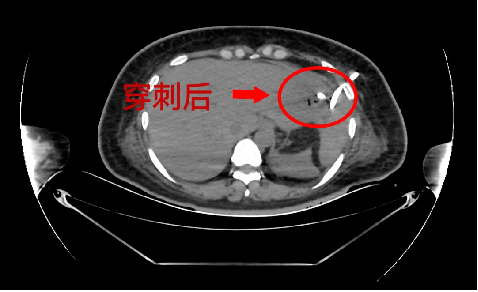

重症医学科主任杨徳军仔细查看患者情况后,结合检查结果,考虑患者是肝脓肿诱发糖尿病酮症酸中毒。急请普外科会诊,普外科学科带头人龚昭教授和副主任医师余勇会诊后,一致诊断患者为急性肝脓肿,立即为患者行CT引导下穿刺置管术,抽取咖啡色样液体送检,并留置引流管引流。引流液培养结果为“高毒力肺炎克雷伯杆菌感染”。经过3天针对性的抗感染治疗及脓液引流,患者生命体征平稳,感染指标下降,成功转入普通科室进一步康复治疗。